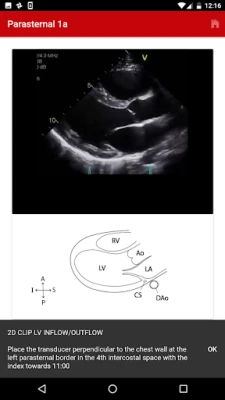

The Echo app provides step-by-step instructions for performing a normal pediatric echocardiogram and uses video clips, images and illustrations to aid in instruction. The app is intended to be used by sonographers at all levels of training, pediatric cardiology fellows, as a teaching aid for pediatric cardiologists and by anyone interested in learning how to perform the normal pediatric echo exam.

There are four standard views where images can be obtained:

1. Subcostal

2. Parasternal

3. Apical

4. Suprasternal

The exact images and the order in which the images and views are obtained varies by institution. Each protocol (subcostal, parasternal, apical or suprasternal) can be followed in order by clicking on the next tab at the bottom of the page or you can click on an individual numbered view within the protocol list to be taken directly to that view. The name of the view and instructions will pop-up automatically at the bottom of the page. The instructions and additional notes can also be found in the “NOTE” button at the bottom of the page.